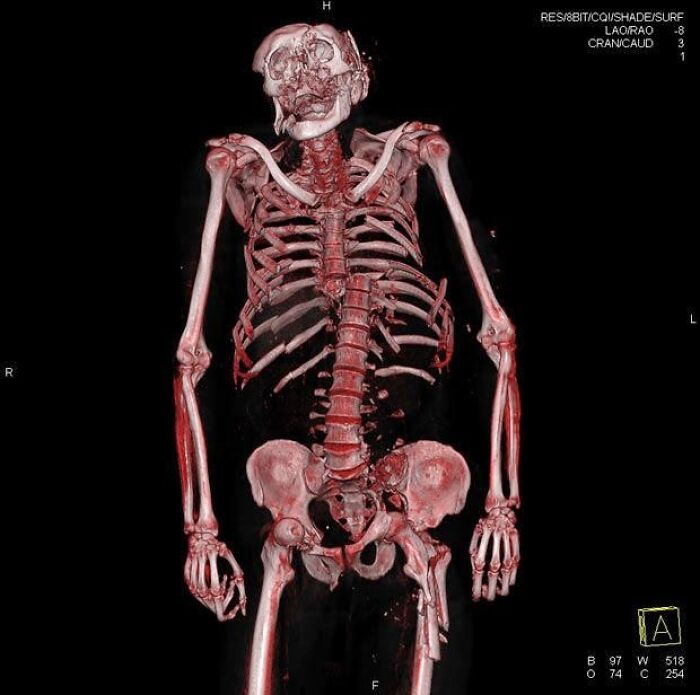

Una lesión de balón prisionero que resultó en una fractura de radio y diáfisis cubital, también conocida como antebrazo roto.

Esta lesión provocó una fractura diafisaria bilateral que afectó tanto al radio como a la diáfisis cubital, presentándose así como una fractura de antebrazo.

Esta lesión en particular implica la discontinuidad disruptiva de los huesos largos situados en la región antebraquial, concretamente las diáfisis del radio y el cúbito.